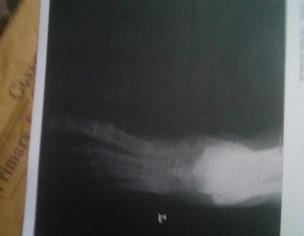

my mother is suffering from a lot of pain in her foot along with redness and swelling she did not had any injury or trauma to the foot. she went to an orthopedic who suggested the test for cbc , kindneys and crp iam attaching the results below . please kindly advice what could be wrong with her ,she has also started having some swelling in one hand now. she is also a patient of arthritis and blood pressure im attaching xrays and reports below

this could be a condition called pseudogout or gout. if she has fever then infection in the joints in an option. better to organize an appointment for further evaluation and management

anti ccp came 8 and Rh factor is negative please guide further

this is either cellulitis or gout. continue the medicine for 3 days. if not improved get a consultion